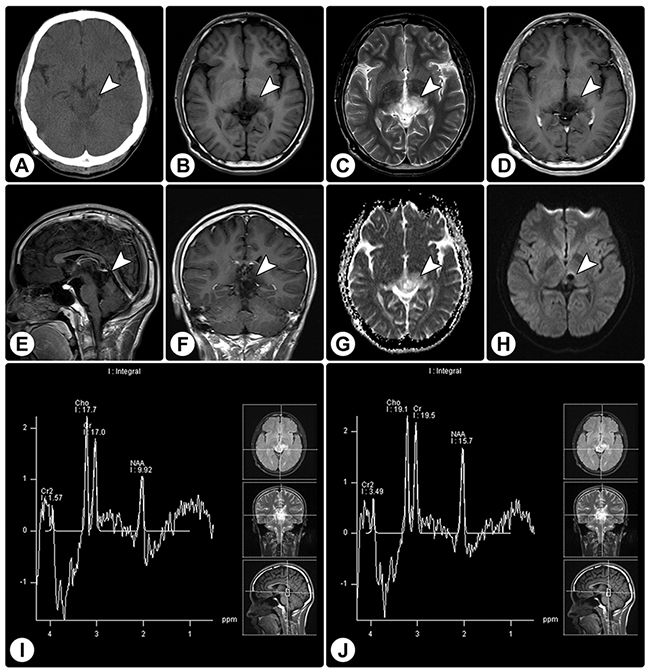

Figure 3: Rosette-forming glioneuronal tumor in the lateral ventricle and cerebellar rosette-forming glioneuronal tumor with a satellite lesion. (A-F) MRI demonstrates a solid mass (arrowheads) in the lateral ventricle, with hypointensity on axial T1WI (A) and hyperintensity on axial T2WI (B). (C and D) Axial (C) and sagittal (D) contrast T1WI show focal enhancement. (E and F) The ADC map (E) and DWI (F) show facilitated diffusion. (G–J) MRI of another patient reveals a solid mass in the cerebellar vermis (arrowheads) and a satellite lesion in the cerebellar hemisphere (arrows); both of these show hypointensity on axial T1WI (G and H) and hyperintensity on axial T2WI (I and J). (K–N) On axial (K and L) and sagittal (M and N) contrast T1WI, the vermis lesion exhibits rim enhancement (arrowheads) and the satellite lesion shows no enhancement (arrows). (O–R) The ADC map (O and P) and DWI (Q and R) show facilitated diffusion.

Figure 4: Radiological and histopathological profiles of a patient with concomitant rosette-forming glioneuronal tumor and schwannoma. MRI reveals a spinal extramedullary solid mass at the C1 level (arrowheads) and an intramedullary solid mass in the medulla oblongata (arrows). (A–C) The former mass shows isointensity on sagittal T1WI (A), slight hyperintensity on sagittal T2WI (B), and homogeneously remarkable enhancement on sagittal contrast T1WI (C). (E–G) The latter mass shows isointensity on sagittal T1WI (E), remarkable hyperintensity on sagittal T2WI (F), and no enhancement on sagittal contrast T1WI (G). (D and H) Histopathological examinations of these 2 lesions are consistent with schwannoma (D) and RGNT (H), respectively. (Original magnification: D: 100×; H: 200×).